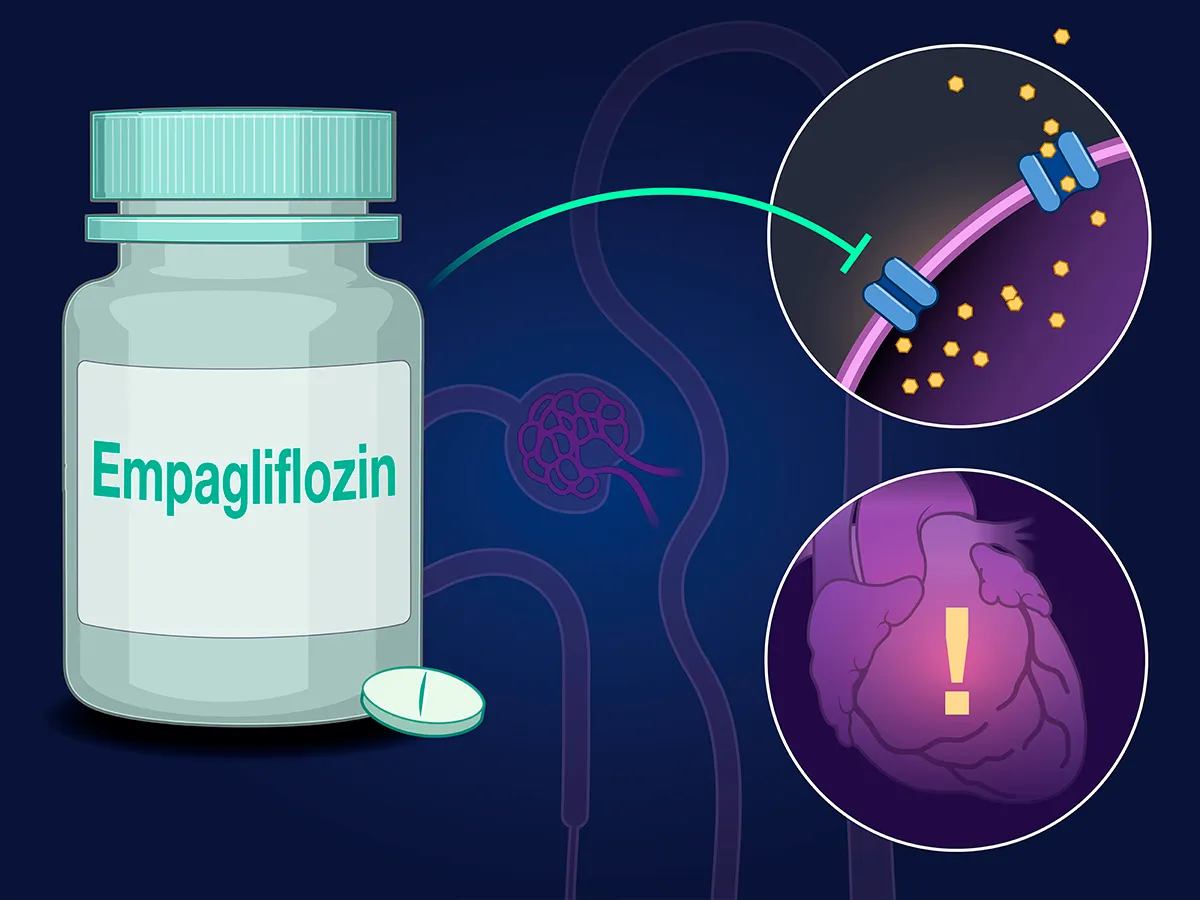

Os cinco estudos que mais impactaram a nefrologia em 2024 parte 2 (Empa-Kidney)

Os cinco estudos que mais impactaram a nefrologia em 2024 parte 2 (Empa-Kidney)O estudo EMPA-KIDNEY mostrou que a empagliflozina reduz a progressão da doença renal e eventos cardiovasculares em pacientes com DRC, com ou sem diabetes. Os benefícios foram consistentes em diferentes subgrupos, destacando os inibidores de SGLT2 como essenciais na prática nefrológica.

Luís Sette

2 anos atrás